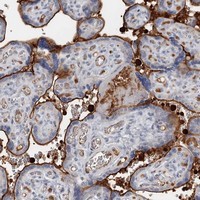

- Main image

- Experimental details

- Immunohistochemical staining of human placenta with SNX22 polyclonal antibody (Cat # PAB23292) shows strong membranous positivity in trophoblastic cells at 1:500-1:1000 dilution.

- Validation comment

- Immunohistochemistry (Formalin/PFA-fixed paraffin-embedded sections)